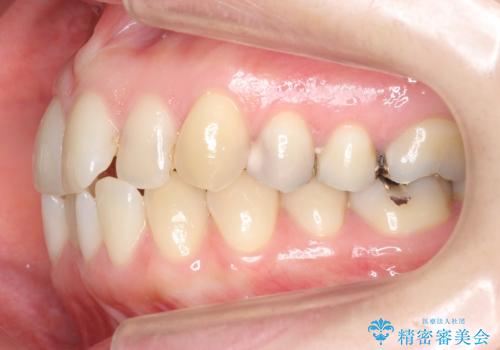

上の前歯が一部引っ込んでいる 下のがたがた マウスピース矯正

- 前歯2本が後ろに引っ込んでいる状態でした。

マウスピースで歯を抜かずに矯正しました。

左上4番は、虫歯治療をして、セラミッククラウンで修復しています。